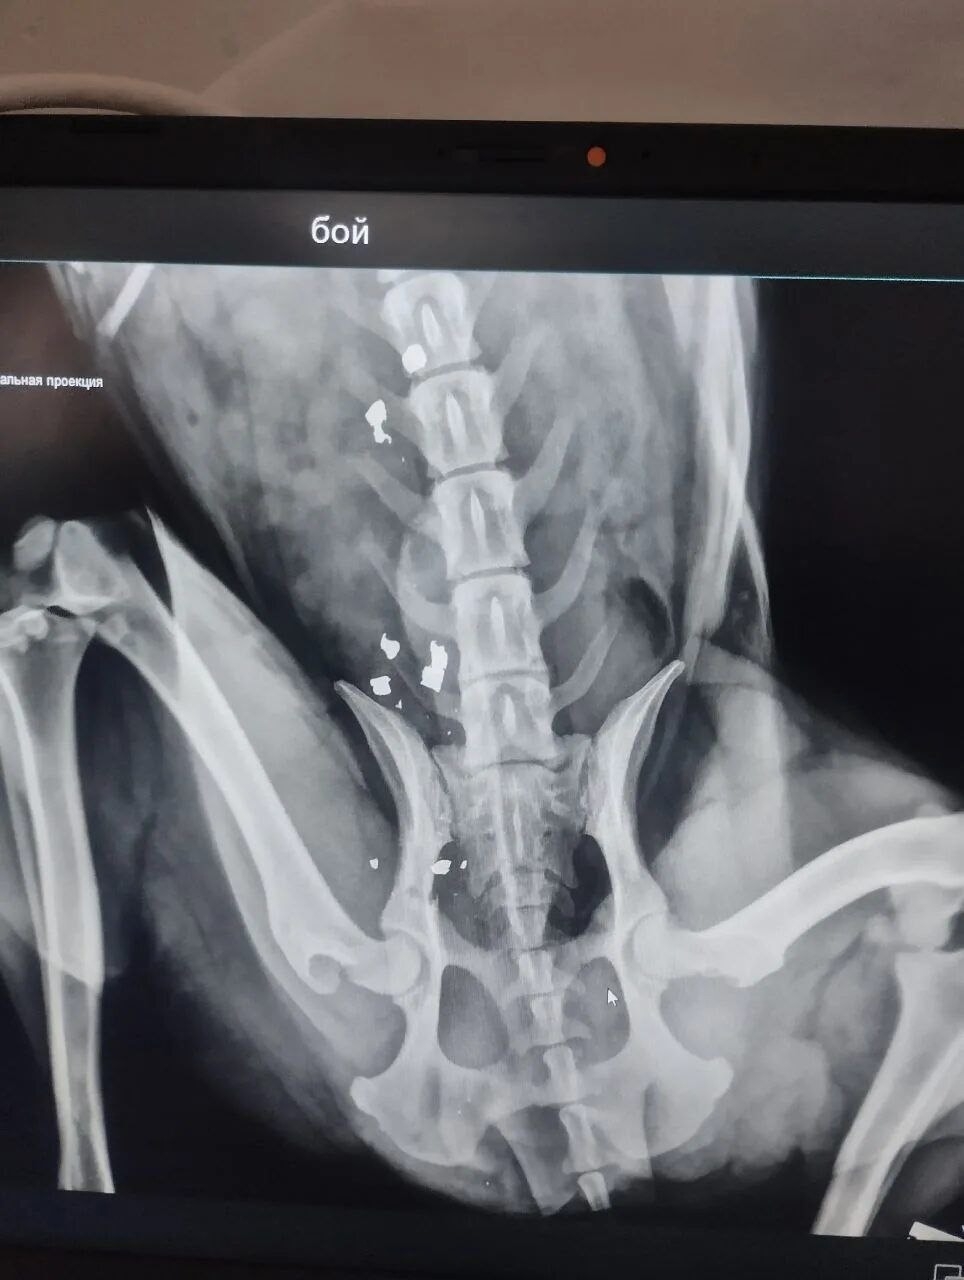

СРОЧНО! ОН ГНИЕТ ЗАЖИВО! 🆘 Щенка расстреляли еще летом, и всё это время он медленно умирает.

Когда-то Боя уже возили в Волгоград на рентген, но полноценного лечения он не получил и снова оказался на улице. Итог — инвалидность и гниющая заживо конечность.